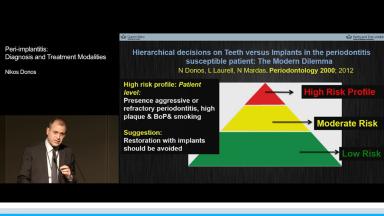

This presentation begins with a discussion of strategic extraction: whether teeth should be extracted as a first choice or kept as long as they function. An overview of estimated numbers of placed and failed implants internationally is given, and differences between the treatment strategies of prosthodontists, periodontists, general practitioners, and surgeons are presented. The definition, prevalence, and risk factors of peri-implantitis and related problems are emphasized. Assessment and diagnosis of peri-implantitis, the importance of radiographic assessment, and evaluation of progressive bone loss are described. The main part of the presentation concentrates on viable treatment options such as antibacterial therapy and ultrasonic debridement, highlighting that prevention is the best treatment.

- discuss prevalence and risk factors for peri-implantitis

- describe the treatment modalities for peri-implantitis